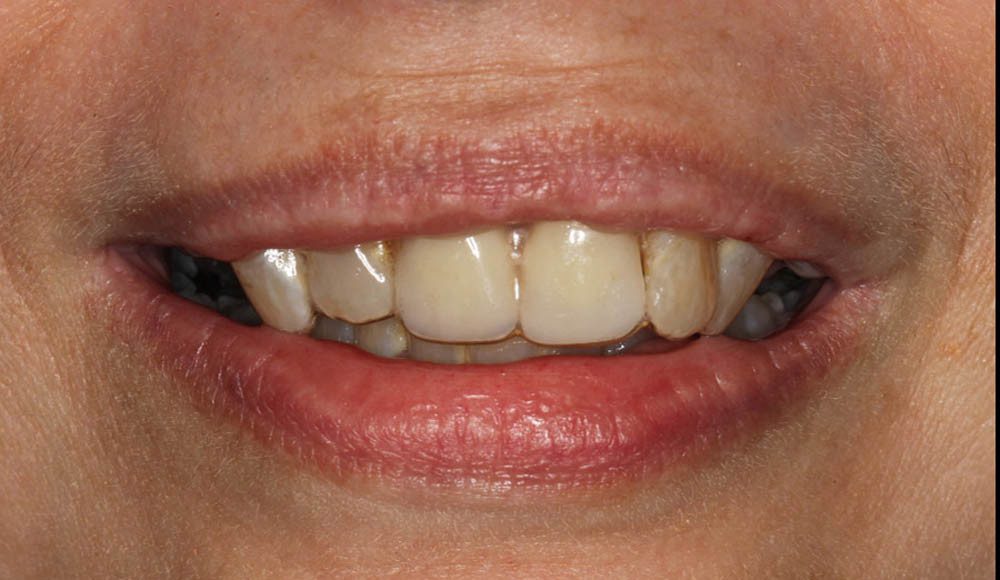

Pre-op smile picture. This patient had been missing her two front teeth for many years. She was wearing an Essix retainer (clear plastic retainer with denture teeth replacing the missing).